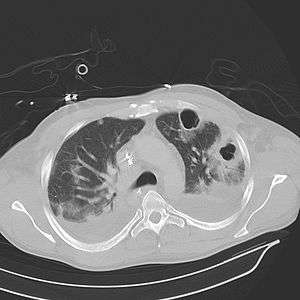

| Computed tomography (CT) scan of chest showing bilateral pneumonia with abscesses, effusions, and caverns. 37-year-old male. | |

Lung abscesses are often on one side and single involving posterior segments of the upper lobes and the apical segments of the lower lobes as these areas are gravity dependent when lying down. Presence of air-fluid levels implies rupture into the bronchial tree or rarely growth of gas forming organism.